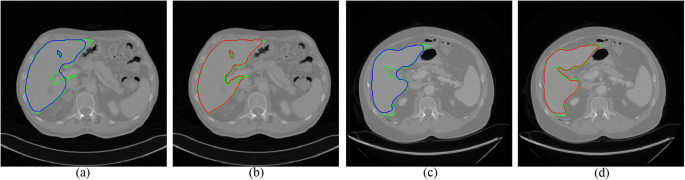

To test on the 3Dircadb1 dataset, we compared the proposed method with interactive graph cut using image intensity only. Figure 6 shows two slices of segmentation results by two methods. The green curves are the ground truth of liver. The blue curves in Fig. 6a,c are the segmentation results using original graph cut. It can be found that some vessels are included. With the help of multi-dimensional graph cut, these vessels can be excluded, as shown in Fig. 6b,d with red curves. The comparison of Dice measure using two methods is shown in Fig. 7. Compared to original graph cut, the mean of Dice measure increases significantly from 0.88 to 0.94.

Two examples of segmentation results by different methods. The ground truth is shown in green curves. (a) and (c) Segmentation using original graph cut (blue curves). (b) and (d) Segmentation using the proposed method (red curves).